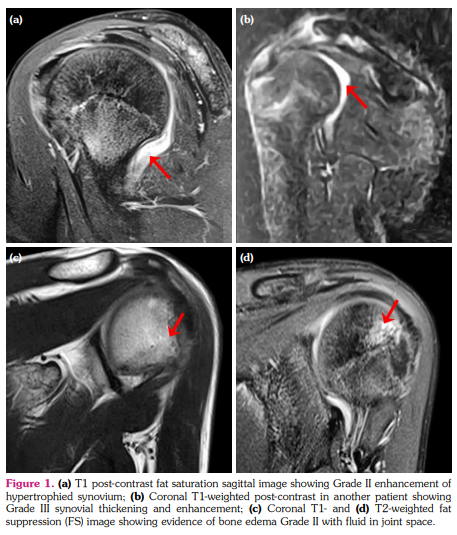

Also, MRI revealed significant joint effusion in 9/32 (28.1%) joints in six patients (Figure 4a, b). Eight of these nine joints had ≥1 JAMRIS component of MRI finding (Supplemental Table 1). Six of these nine joints had synovial hypertrophy (Grade I- 1 joint, and Grade II- 5 joints). Four joints each showed cartilage lesions and bone erosions, respectively. Bone marrow edema was seen in seven joints. It was also noted that six (66%) of the nine joints (4 patients) that had effusion did not fulfil the definition of clinical arthritis.

In addition, the presence or absence of synovial effusion on MRI was also noted. Joint effusion was seen as hyperintensity adjacent to synovium on post-contrast T1-weighted images.